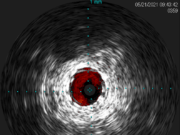

The latest innovation in intravascular ultrasound: Reconnaissance PV .018 OTW digital IVUS catheter

This advertorial is sponsored by Philips.

Intravascular ultrasound (IVUS) is now used in a wide variety of peripheral vascular interventions after having first been utilized...

Use of IVUS reduces patient risk of MALE or death by up to 28%:...

The benefits of utilizing intravascular ultrasound (IVUS) in peripheral vascular interventions has been widely demonstrated in the literature. In...